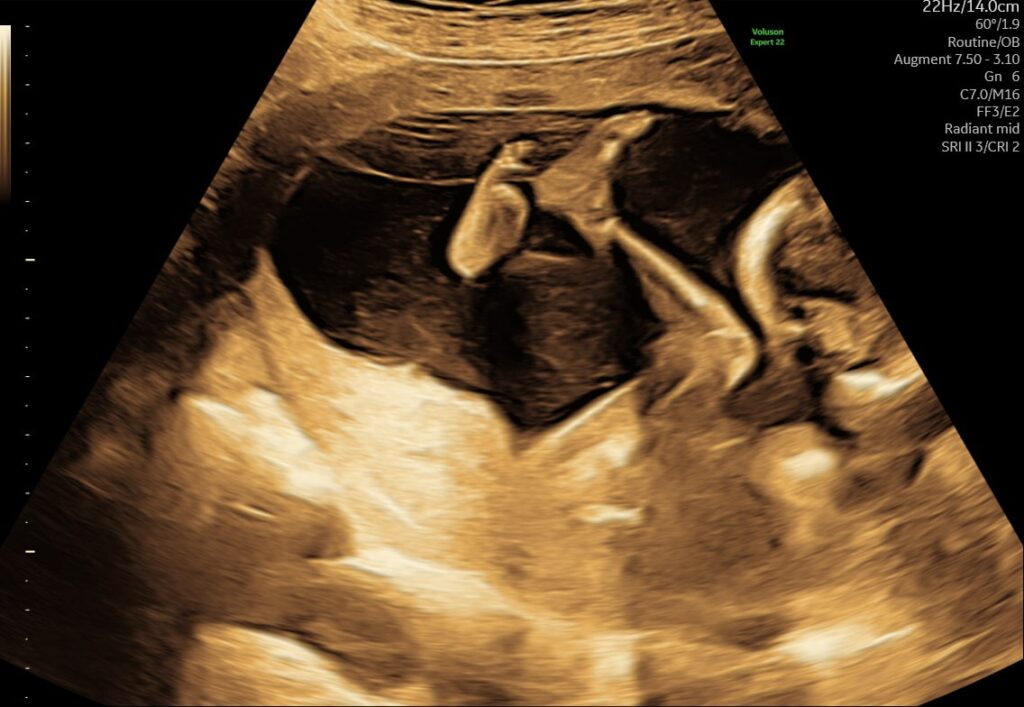

(32+0 til 32+6)

Barnet tager i denne uge markant på i vægt, og det begynder at fylde næsten hele livmoderen. Pladsen bliver trang, men udviklingen fortsætter hurtigt – både fysisk og mentalt. Skulle barnet blive født nu, vil det have meget gode chancer for at klare sig uden store komplikationer.

- Stillingen: Mange babyer har vendt sig med hovedet nedad, men det er stadig normalt, hvis det ikke er sket endnu – der er plads til at vende sig et par uger endnu.